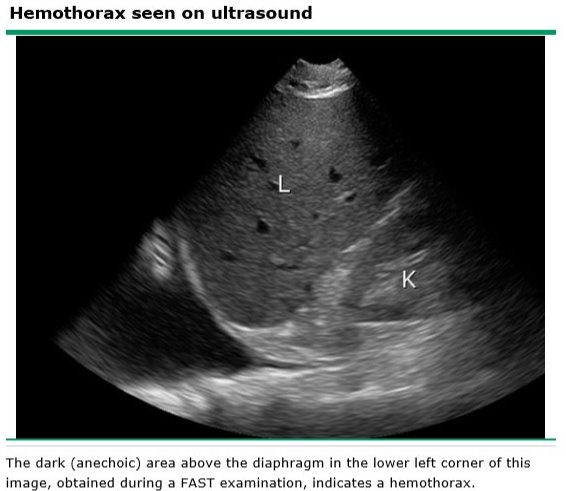

When is surgery indicated in a clotted hemothorax?

[surgery in 1st week to avoid peel]

[UpToDate: Hemothorax is treated with tube thoracostomy using a large (minimum 36 French) chest tube. Immediate bloody drainage of ≥20 mL/kg (approximately 1500 mL) is generally considered an indication for surgical thoracotomy. Shock and persistent, substantial bleeding (generally >3 mL/kg/hour) are additional indications. Vital signs, fluid resuscitation requirements, and concomitant injuries are considered when determining the need for thoracotomy.